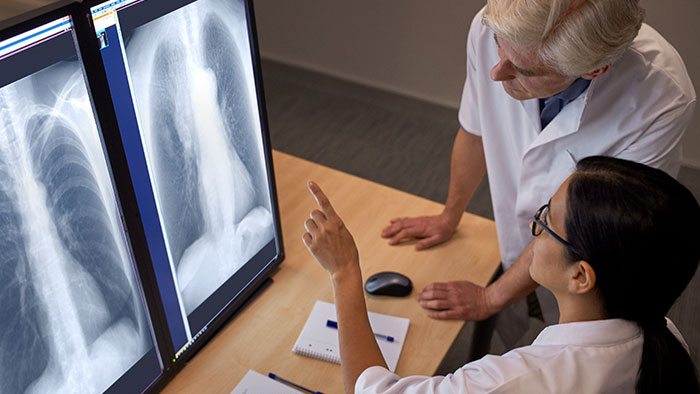

Les équipements de radiographie et de fluoroscopie de Philips offrent des processus de travail intuitifs et des images de qualité afin d’améliorer le rendement et de permettre des diagnostics fiables tout en augmentant la satisfaction du personnel et des patients. Il n’y a pas de limite à ce que nous pouvons faire ensemble. Parce qu’aujourd’hui, la santé ne connaît aucune limite, et qu’il doit en être de même pour les soins.